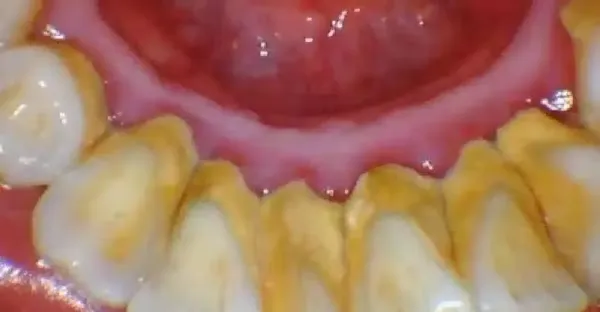

牙結石:巧妙的去掉討人厭的牙結石,一起來學習一下吧